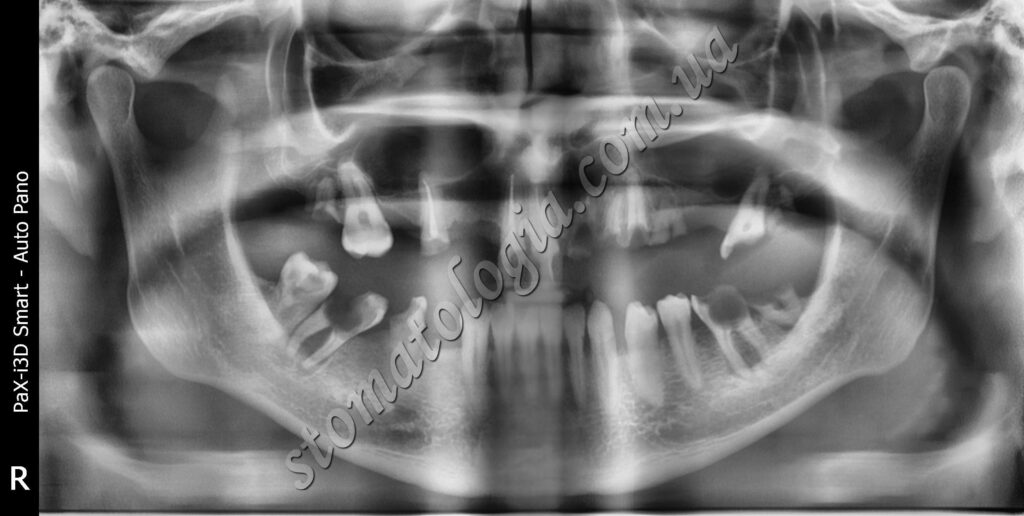

Ретиноване ікло верхньої щелепи спричинило запалення. Ретиновані також усі зуби мудрості